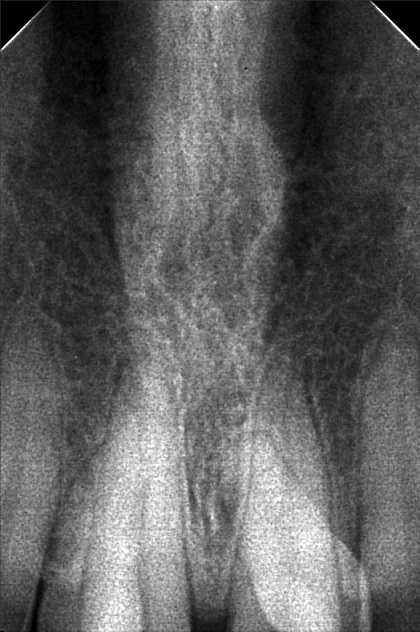

- 8/20/22- Checkup of supernumerary tooth (mesiodens), suggested extraction and ortho tx 9/10/22 - EXO SUPERNUMERARY (MESIODENS) #12, #22, Given post op instructions, prescribed mefenamic acid 500mg for pain 11/04/22-installation of braces/OP 12/3/22- adj 01/07/23- ADJ 02/10/23-ADJ/LC 04/15/23- Removal of Coil Spring/ same wire/ Chain #13-16/ #23-26 05/16/23- Ortho/U - SS- 18 L - Same wire/Ligature wire #12-#22/Chain #13-#16; #23-#26/Fox class 2 07/14/23- same wire reattachment 34 08/18/23- Chain Upper/ Box elastic 14-15 to 44-45/24-25 to 34-35 09/16/23- same wire/ chain U 10/14/23- 16x16ss U 18ss L 11/15/23- ADJ 16x16 U 16x 16 L 12/09/263- same wire, Extrude #11,21 01/13/24 same wire RW on #43 distal chipmunk 13-43 02/10/24- adj 18ss upper LC 37- Occlusal/ mesial class II 03/16/24 Adj stabilation of bite same wire l;ast wire next meeting 16x22 NITI 04/27/24 16x22 NITI cross elastic on posterior all Q 05/01/24 reattachment #26 05/18/24 Adj same wire LC #36 Occlusal #11 mesial (in) #23 mesial (out) 07/27/24 Adj same wire ligature wire 08/24/24 same wire chain U/L 10/19/24 removal of brace with retainer 02/15/25 LC #16,#17 Occ+lingual pit 03/22/25 LC #26 lingual pit class II mesial OP 12/27/25 Oral Prophylaxis - light Xray LC #46 - OCC #47 - OCC #36 - Distal, Occ #37 - Mesial, Occ 01/24/26 Rx. prednisone

- napolitano_ojiah_02.jpg

- ojiah_may_napolitano.jpg